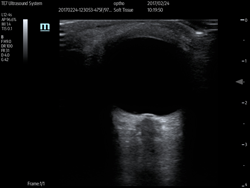

Point-of-Care Ultrasound (POCUS)

Point-of-care ultrasound (POCUS) is a focused ultrasound exam clinician performs at the bedside. POCUS exams improve the accuracy, quality, and efficiency of clinical care.

Examples